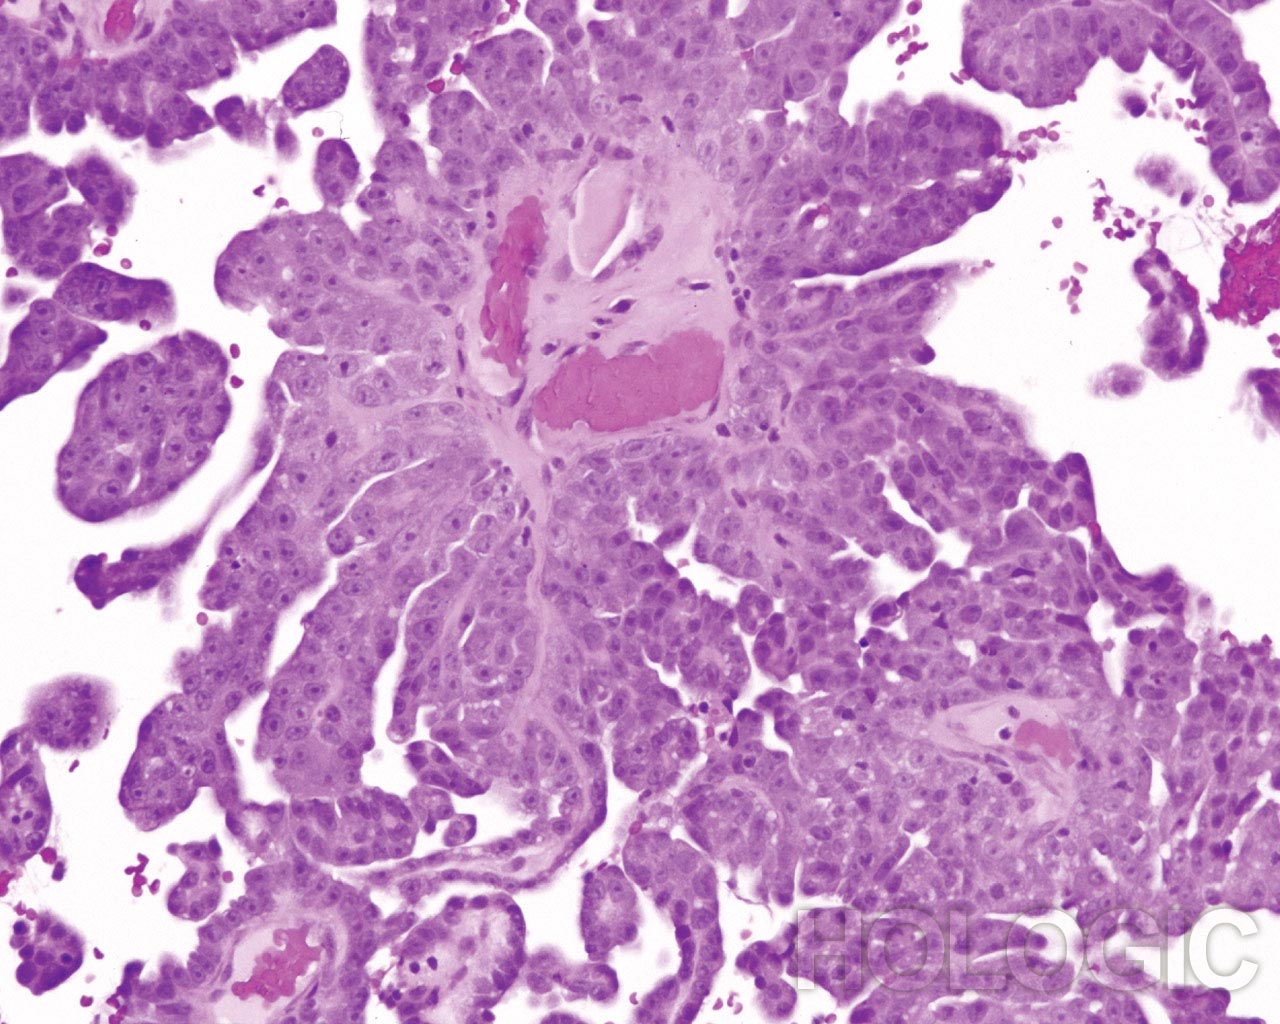

Biopsy

Papillary serous carcinoma of the endometrium

Same Patient, Split Sample